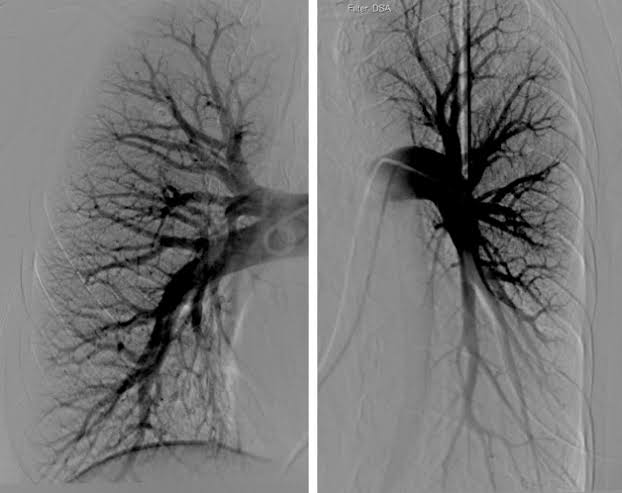

Pulmonary angiography (પલ્મોનરી એનજીઓગ્રાફી):

- આ એક ઇન્વેસીવ ફ્લુરોસ્કોપીક પ્રોસીઝર છે જેની મદદથી પલ્મોનરી વેઇન અને પલ્મોનરી આર્ટરીને વિઝયુલાઇઝ કરી શકાય છે.

- જેમાં ફિમોરલ આર્ટરી અથવા પલ્મોનરી આર્ટરીમાં કેથેટરની મદદથી કોન્ટ્રાસ્ટ ડાય ઇન્જેકટ કરવામાં આવે છે અને પલ્મોનરી વેસલ્સને વિસયુલાઈઝ કરવામાં આવે છે અને તેની સ્ટડી કરવામાં આવે છે.

- પલ્મોનરી એનજીઓગ્રાફીની મદદથી પલ્મોનરી એમ્બોલીઝમ, પલ્મોનરી વસ્કયુલર, પલ્મોનરી હાઇપરટેન્શન તેમજ પલ્મોનરી વસ્કયુલર ટ્રી ની એબનોર્મલીટી ડિટેકટ કરી શકાય છે તેમજ પલ્મોનરી બ્લડ ફલો, બ્લોકેજ, પ્રેશર અને એબનોર્મલીટીને ઇવાલ્યુટ કરવામાં આવે છે.